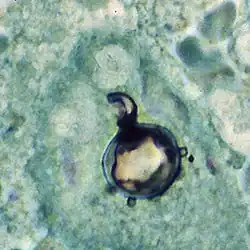

The yeast reproduces by asexual budding, where daughter cells are borne asynchronously at multiple, random positions across the cell surface. Buds begin by layers of cell wall increasing in optical density at a point that eventually gives rise to the daughter cell.[3] Once the bud has expanded, a cleavage plane develops between the nascent cell and the mother cell. Following dehiscence, the bud scar disappears.[8] In tissue, budding occurs inside the granulomatous center of the disease lesion, as visualized by hematoxylin and eosin (H&E) staining of histologic sections.[10] Nonbudding cells measure 5–15 μm in diameter, whereas those with multiple spherical buds measure from 10–20 μm in diameter.[10] In electron microscopy, cells with multiple buds have been found to have peripherally located nuclei and cytoplasm surrounding a large central vacuole.[12] In the tissue form of P. brasiliensis, yeast cells are larger with thinner walls and a narrower bud base than those of the related dimorphic fungus, Blastomyces dermatitidis.[10] The yeast-like form of P. brasiliensis contains multiple nuclei, a porous two-layered nuclear membrane, and a thick cell wall rich in fibers, whereas the mycelial phase has thinner cell walls with a thin, electron-dense outer layer.[8]

Paracoccidioides brasiliensis causes mucous membrane ulceration of the mouth and nose with spread through the lymphatic system. A hypothesized portal of entry for the fungus to the body is through the periodontal membrane.[30][31] The route of infection is assumed to be inhalation following which the infective propagule gives rise to the distinctive multipolar budding yeast forms in the lung resembling a "ship's wheel" seen in histological sections.[9][32] Both immunologically normal and compromised people are at risk for infection.[9] The lungs, lymph nodes, and mucous membrane of the mouth are the most frequently infected tissues.[10] The pathological features of paracoccidioidomycosis are similar to those seen in coccidioidomycosis and blastomycosis.[33] However, in the former, the lesions first appear in the lymphoid tissue and then extend to mucous membranes,[33] producing localized to diffusive tissue necrosis of the lymph nodes.[33] The typically extensive involvement of lymphoid tissue and the limited occurrence of the gastrointestinal tract, bone and prostate set the clinical picture of paracoccidioidomycosis apart from that of blastomycosis.[10][33]